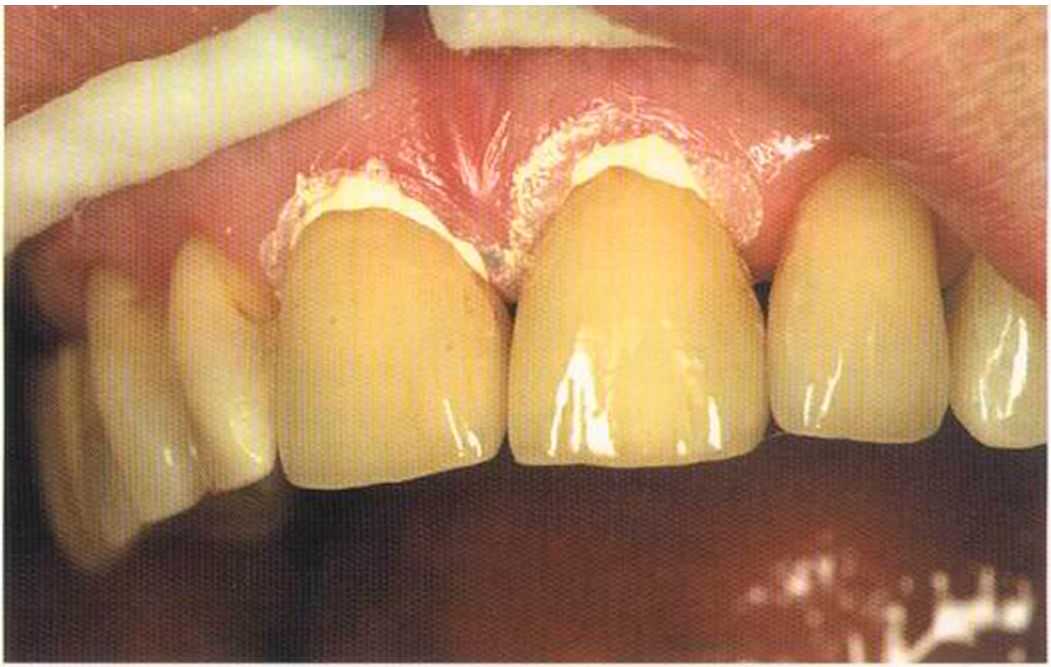

Зафиксированные на цемент коронки в полости рта. Видны излишки цемента, которые потом легко удалить, они отскакивают, как яичная скорлупа.

Только что зацементированные коронки. До сих пор сохранилось воспаление десневого сосочка. Уже через несколько дней он будет здоровым, бледно-розового цвета.